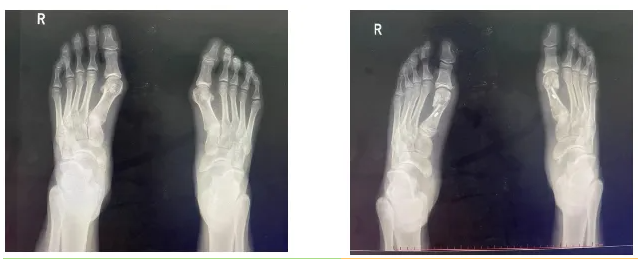

拇外翻是指拇趾在第一跖趾关节处向外偏斜,超出正常生理范围。其形成原因可能包括先天因素(如足部结构异常)或后天因素(如长期穿着不合适的鞋子)。

外观变化:大脚趾向外偏斜,足部横弓可能变宽。

拇外翻可能导致足部疼痛和形态改变,影响日常活动。在临床治疗中,微创手术是可选的治疗方式之一。